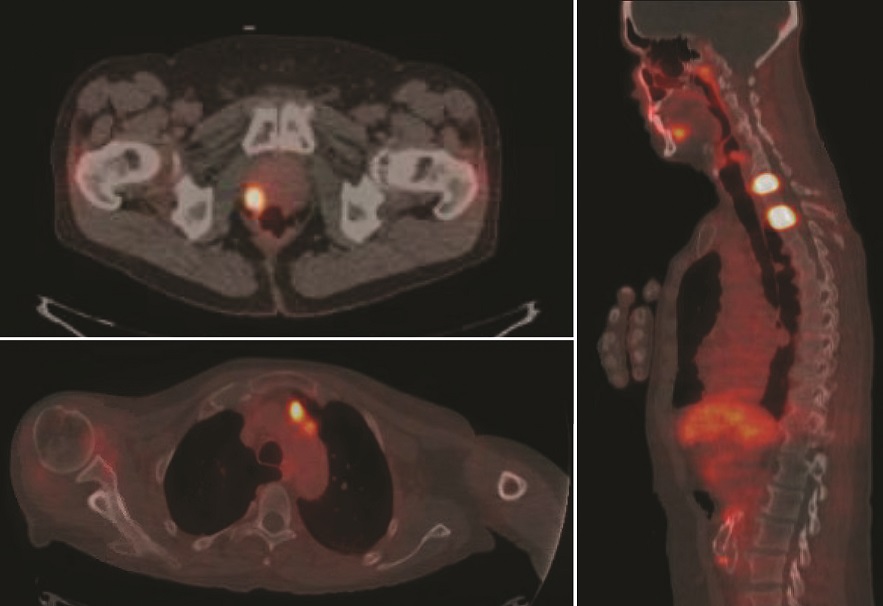

Ridley-Tree’s Nuclear Medicine Department is now

using a radioactive agent called PYLARIFY® (F18-PSMA)

to provide more accurate and earlier detection of prostate

cancer than our previous imaging methods. This diagnostic

tracer, approved by the FDA in May 2021, helps physicians

in two scenarios: 1) when a patient is newly diagnosed

and the physicians want maximum information about the

prostate cancer’s location before treatment, and 2) when a

patient who was previously treated for prostate cancer has

a blood test that suggests cancer has returned.

F18-PSMA / PET-CT

imaging has greatly

advanced how urologists

and oncologists can

view prostate cancer

metastases and how

they stage the disease. In

patients with an elevated

prostate specific antigen

(PSA), Pylarify® was able

to detect the location of

the recurrent disease in

nearly 2 out of 3 patients,

when the disease was undetectable by prior imaging methods.